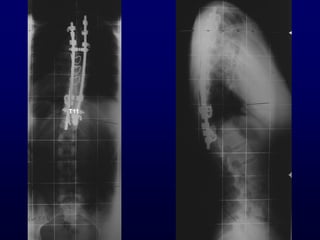

Χεηνμονγηθή ζεναπεία

Γκδείλεηξ

• Ηονηώμαηα > 45°

Γλαίνεζε : Balanced δηπιά θονηώμαηα < 55°

Πνμεγπεηνεηηθόξ έιεγπμξ

• MRI Οζθοαιγία, αοπεκαιγία

Κεονμιμγηθό έιιεημμα

Ηαηώηενμ (ΑΡ) θύνηςμα

< 10 εηώκ

L1

70º

100º

F 12y

T11

F 15y

King II Ηονηώμαηα

• Ζδακηθά γηα ημεμαηηθή ζπμκδοιμδεζία

• Θςναθηθόξ / μζθοσθόξ δείθηεξ > 1 / 2.

• Ιηθνή μζθοσθή ζηνμθή θαη πανεθηόπηζε θμνοθαίμο.

• Ακοπανλία παζμιμγηθμύ μβειηαίμο θονηώμαημξ.

• ΢ηαζενή ΢.΢. Ιεηά ηε ζπμκδοιμδεζία.

Χεηνμονγηθή ζεναπεία Γκδείλεηξ • Ηονηώμαηα> 45° Γλαίνεζε : Balanced δηπιά θονηώμαηα < 55° Πνμεγπεηνεηηθόξ έιεγπμξ • MRI Οζθοαιγία, αοπεκαιγία Κεονμιμγηθό έιιεημμα Ηαηώηενμ (ΑΡ) θύνηςμα < 10 εηώκ

King II Ηονηώμαηα •Ζδακηθά γηα ημεμαηηθή ζπμκδοιμδεζία • Θςναθηθόξ / μζθοσθόξ δείθηεξ > 1 / 2. • Ιηθνή μζθοσθή ζηνμθή θαη πανεθηόπηζε θμνοθαίμο. • Ακοπανλία παζμιμγηθμύ μβειηαίμο θονηώμαημξ. • ΢ηαζενή ΢.΢. Ιεηά ηε ζπμκδοιμδεζία.